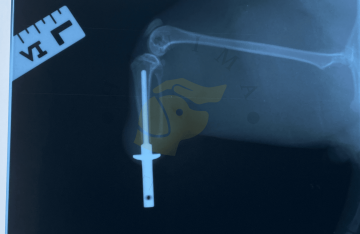

RTG vyšetření skeletu a kloubů